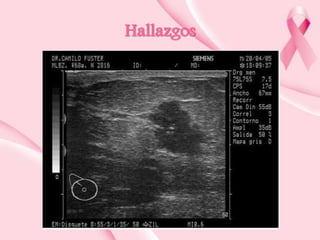

Hallazgos en técnicas de imagen

Carcinoma invasivo/infiltrante

• Nódulo

• Hipoecoico

• Márgenes espiculados

• Mal definidos

• Con angulacion

• Sombra posterior

• Eje vertical mayor al horizontal

Hallazgos